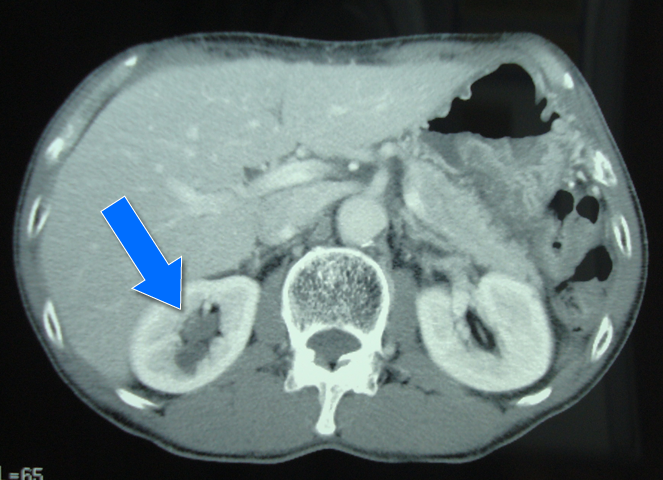

画像診断をお願いしているクリニックでは、以前は腹部なら腹部、胸部なら胸部だけを丁寧に撮影して読影してくれた。それで十分なのだが、最近は腹部をオーダーした時には肺の一部を、胸部をオーダーした時には腎臓のある位置まで撮影してくれるようになった。CTの撮影時間はかなり早くなっているので、ざっと大まかな全体像を作るのは訳ないことだ。しかし、保険診療では撮像部位によって保険点数のルールが決まっているから、オーダーが肺癌の疑いであれば、勝手に腹部CTを撮るわけにはいかない。しかし、本稿で示すように、位置決めの準備のための撮像で、偶発的に何か発見をすることが増えてきたのだと思う。放射線診断医にとって、それを見過ごすわけにはいかない。AさんのCT画像でも、同時に撮像された腎臓に結石と右腎盂に軟部組織濃度を示す腫瘤が見つかった。後日造影CTを行って、それが腎盂癌である可能性が高まったため、専門医療機関に紹介。7月19日に右腎尿管全摘+膀胱カフ状切断術を行い、完治となった。